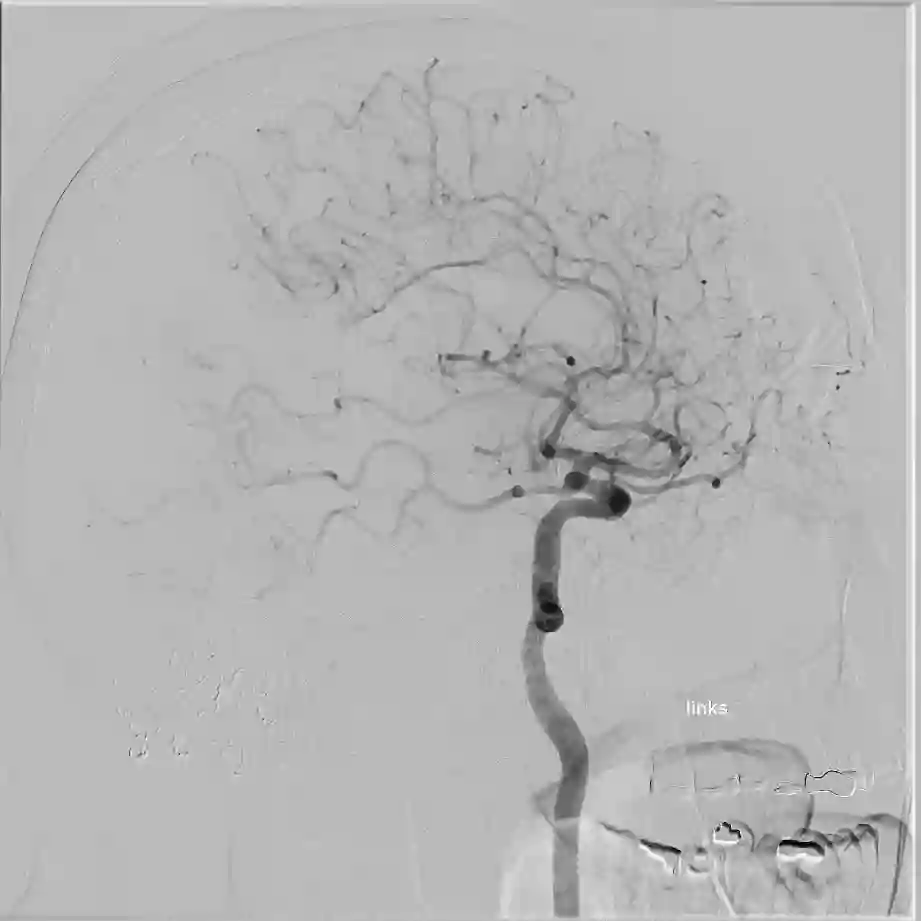

Angiographie

ICA Angiographie mit Knochen

Darstellung einer ICA digitalen Subtraktionsangiographie mit knöchernen Strukturen des Schädels.